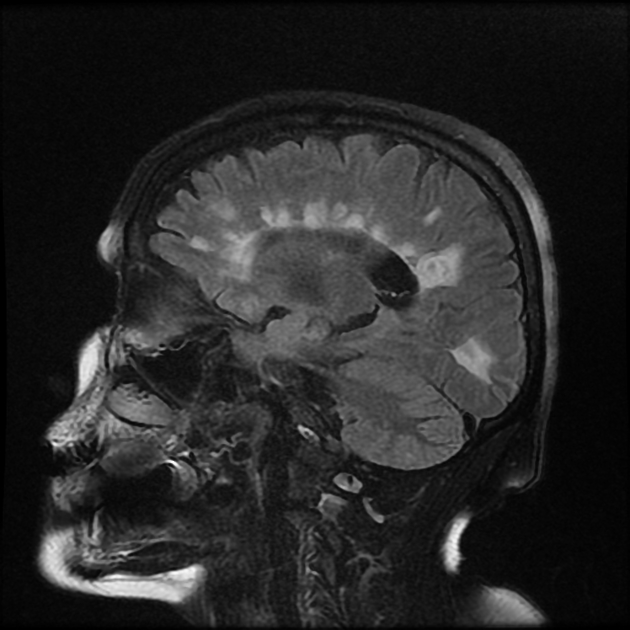

Clinical Case Challenge   Dear Friend, This week, I wanted to do something different. Every week, you guys read this newsletter and my experiences of medicine, work and life in general. This week, I wanted to put you guys to a little test with a clinical case....